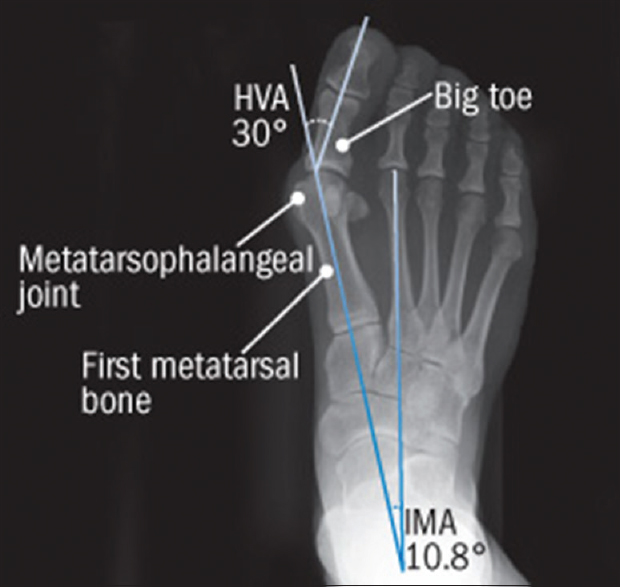

HV deformity is classified by the degree of deformity as assessed by weight-bearing anteroposterior radiographs [Figure 4] as follows:

- Mild deformity is defined by intermetatarsal angle (IMA) of <13° and HV angle (HVA) of <30°

- Moderate deformity is defined by IMA >13° but HVA of <40°

- Severe deformity is characterized by IMA of >20° and HVA >40°.